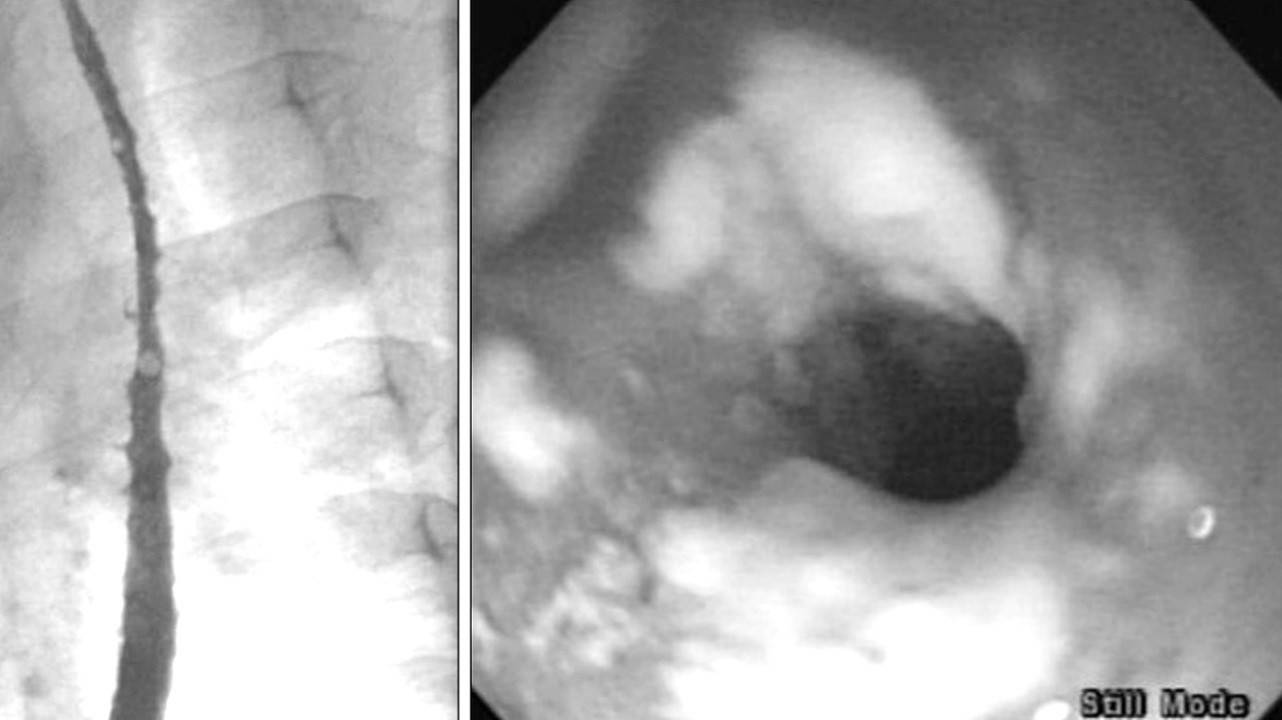

Наиболее распространенным микозом является кандидоз , который вызывают дрожжеподобные грибы рода Кандида (Candida). Чаще всего возникает кандидоз слизистых оболочек полости рта и женских половых органов, который называют молочницей. Кроме того, кандида может поражать верхние дыхательные пути, легкие, кишечник и другие органы.

Кандидоз пищевода. Фото: Pediatric gastroenterology, hepatology & nutrition / Open-i (CC BY-NC 4.0)

Кандидоз пищевода. Фото: Pediatric gastroenterology, hepatology & nutrition / Open-i (CC BY-NC 4.0)

Один из самых распространенных глубоких микозов – аспергиллез. Вызывается он плесневыми грибами рода Aspergillus, которые образуют белую или зеленоватую плесень на гнилых деревьях, стружках, овощах, фруктах, хлебе, домашних заготовках, сухофруктах, комнатных растениях. Нередки они и в жилых помещениях с подтекающими трубами, сырыми стенами и потолками, в вентиляционных системах и кондиционерах. Если человек, находясь в таком помещении, сделает глубокий вдох, споры этих грибков, рассеянные в воздухе, попадают в бронхи и легкие. В результате у людей, страдающих тяжелыми заболеваниями или имеющих сниженный иммунитет, может может возникнуть отравление и развиться аспергиллезный микотоксикоз.

Аспергиллома мочеточника. Фото: Yonsei medical journal / Open-i (CC BY-NC 3.0)

Аспергиллома мочеточника. Фото: Yonsei medical journal / Open-i (CC BY-NC 3.0)